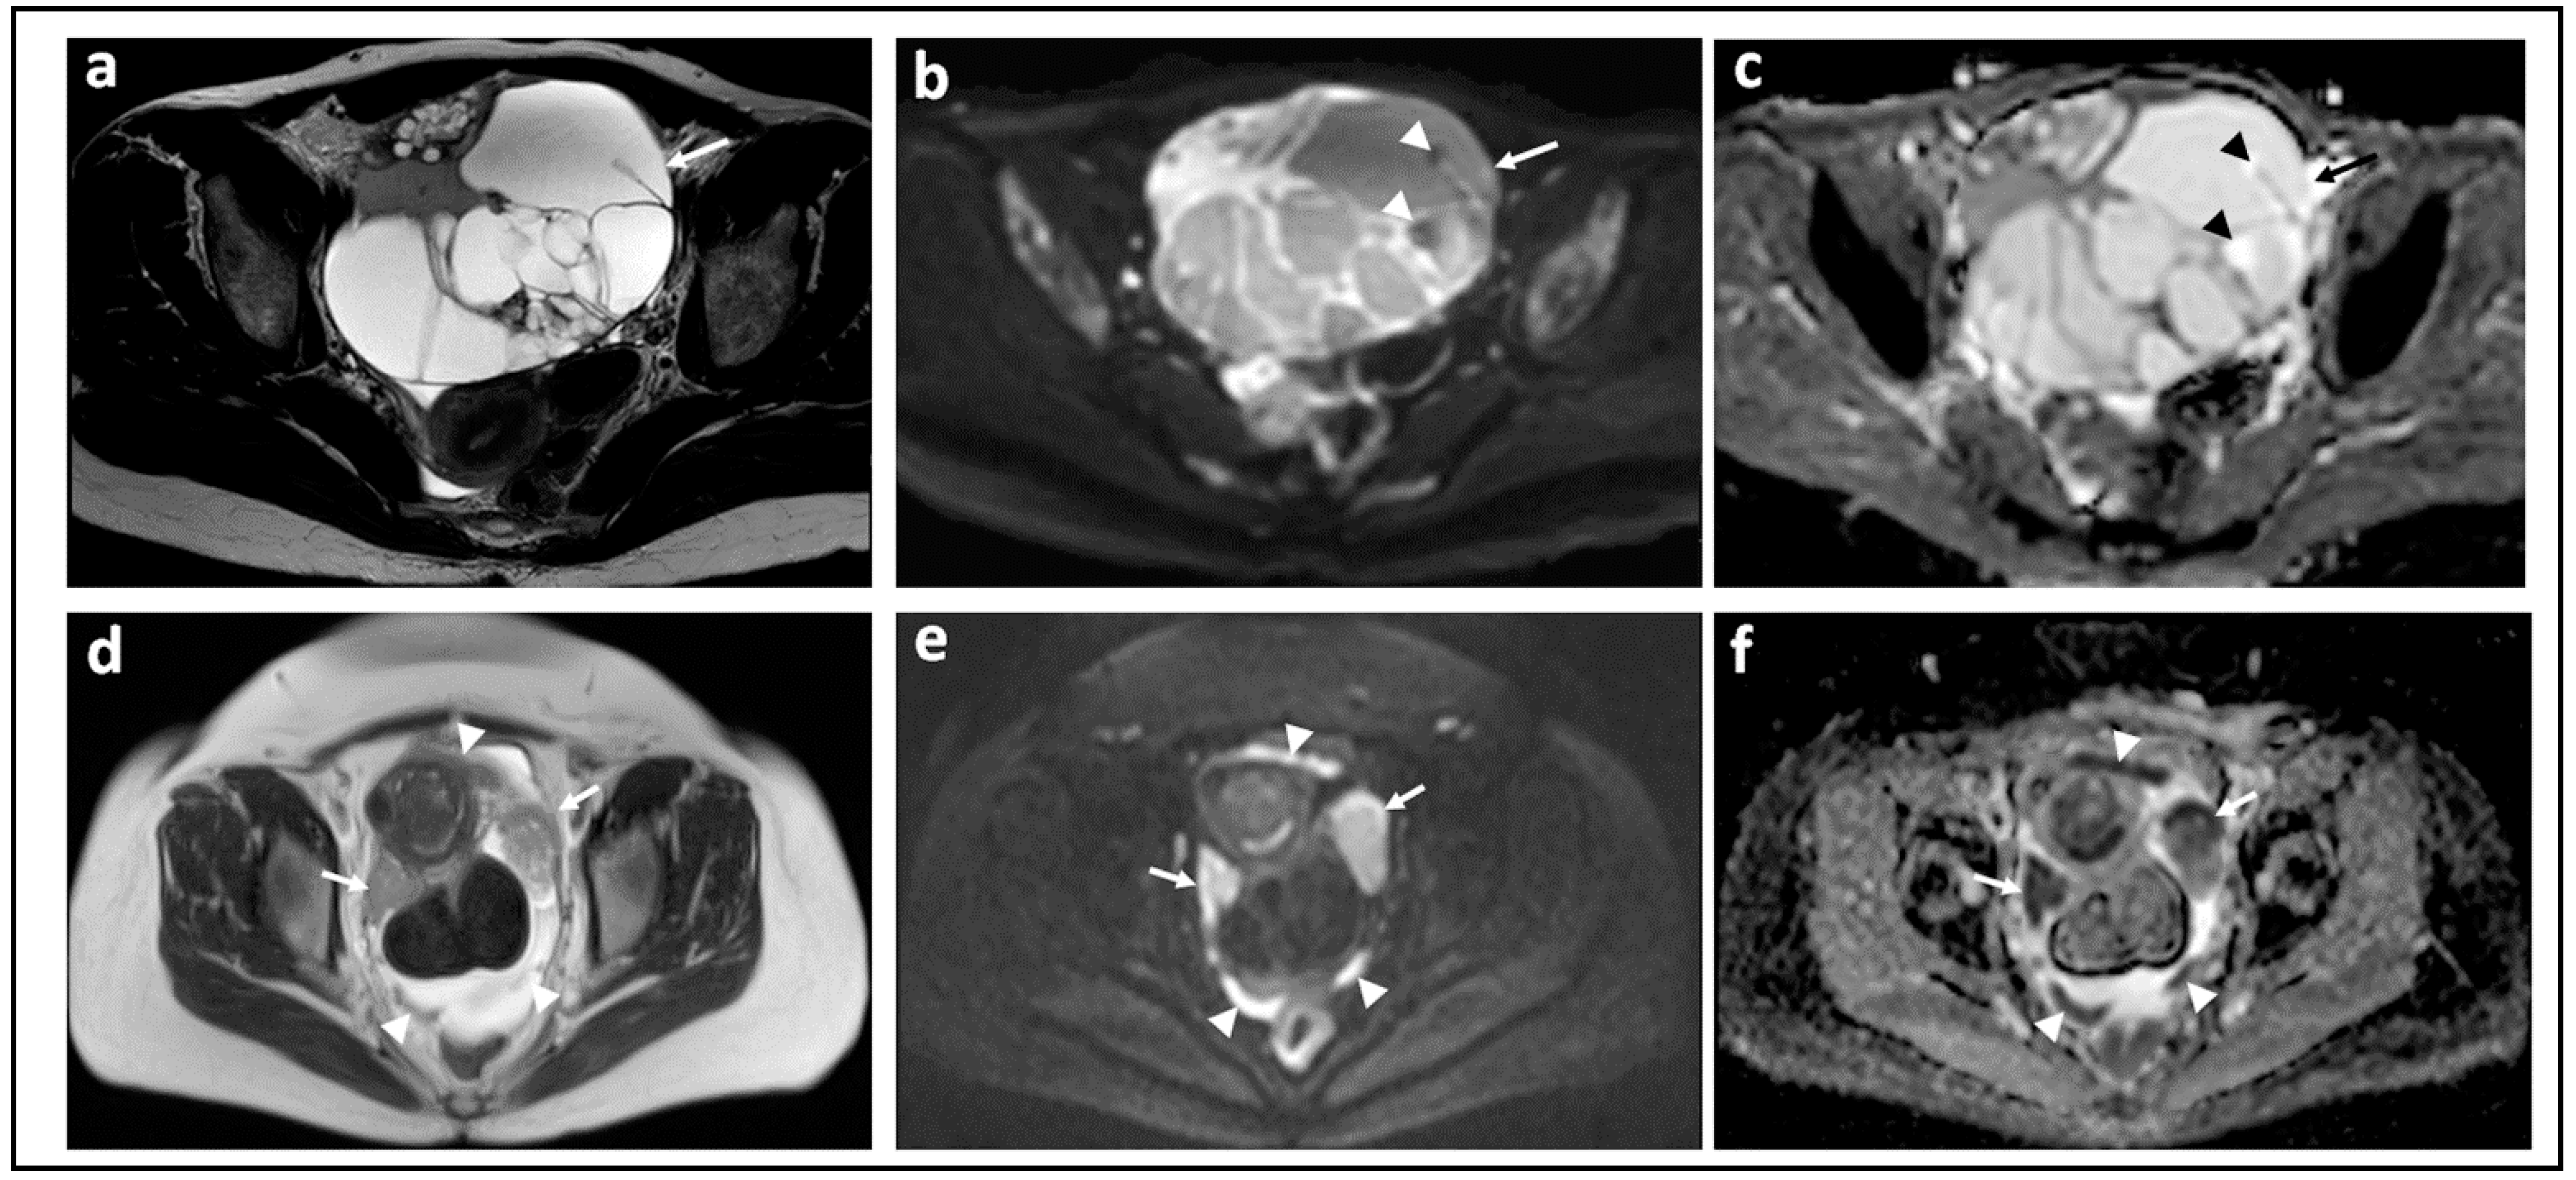

Figure 2.

Borderline versus malignant ovarian tumor: T2-W image (a) and corresponding b = 1000 s/mm2 DW-MRI (b) and ADC map (c) through the mid-pelvis in a patient with a mucinous borderline tumor of the left ovary. There is a large multiloculated cystic mass with no significant solid components (arrows). Two small foci of low signal in (b) show no evidence of diffusion restriction in c (arrowheads). In comparison, the T2-W image (d), b = 900 s/mm2 DW-MRI (e), and ADC map (f) in a patient with invasive high grade serous ovarian cancer show bilateral solid irregular ovarian masses (arrows) and linear peritoneal metastases [arrowheads], all of which show marked diffusion restriction.